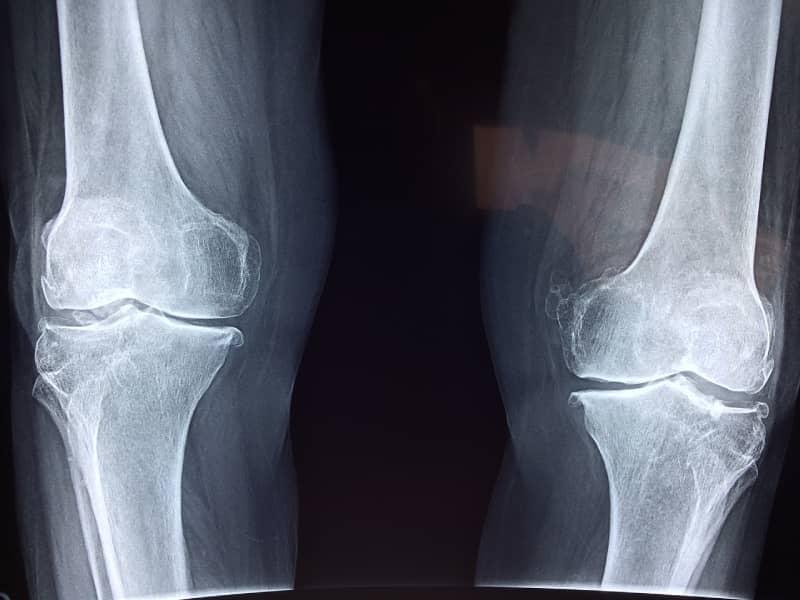

- Knee Replacement

- Osteoarthritis

(گھٹنے کی تبدیلی) - Knee Pain (گٹھنے میں درد)

Orthopedic operations are of several different types and can be done under local anesthesia, spinal anesthesia or general anesthesia. We offer all types of orthopedic operations from Fracture and Trauma treatment, sports injuries and arthroscopic (Camera) surgery to total hip, total knee, total shoulder, and total ankle replacement.